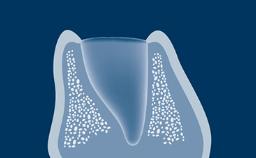

拔牙后,支撑牙齿的牙槽骨会随着时间的推移而发生吸收。这种吸收会导致牙槽骨量减少,如此右上中切牙缺失的临床示例所示。颊舌向骨宽度显著减小,这与将种植体植入以修复为导向确定的正确三维位置的口腔种植基本要求存在冲突。当牙槽骨发生吸收后,通常需要增加骨量以确保可以正确植入种植体且种植体完全嵌入骨中。本模块将介绍一种称为引导骨再生 (GBR) 的特定骨增量技术。